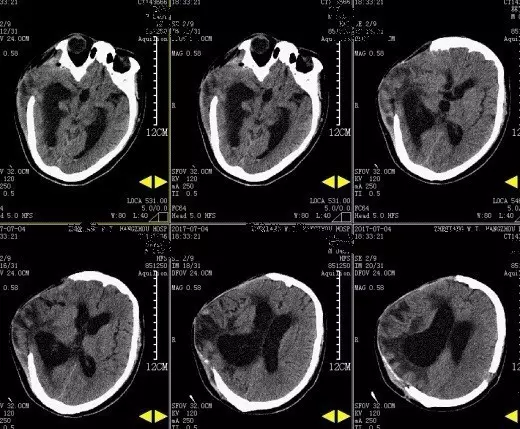

2017年5月7日上海某医院头颅CT提示:颅脑术后,双侧额颞顶部硬膜下积液积血(图4)。于2017年5月9日行双侧钻孔引流术,2017年5月12日头颅CT提示:钻孔术后改变,颅内积气(图5)。患者术后头痛症状持续加重,出现意识不清,5月15日再次复查头颅CT提示脑肿胀明显(图6),于5月17日再次行右侧硬膜下血肿清除+左侧硬膜下血肿钻孔引流术,术后患者出现脑疝,于2017年5月21日行右侧额颞顶扩大去骨瓣减压术+血肿清除术。(图7)

图4. 5月7日头颅CT提示双侧硬膜下积血积液。

图5. 2017年5月12日复查头颅CT提示:钻孔术后改变,颅内积气。

图6. 2017年5月15日头颅CT显示脑沟脑池不清晰,脑肿胀明显。

图7. 2017年5月22日外院头颅CT提示:右侧额颞顶部去骨瓣术后改变。

图8. 2017年7月4日本院头颅CT提示:右侧额颞顶部去骨瓣术后改变,脑室扩张。